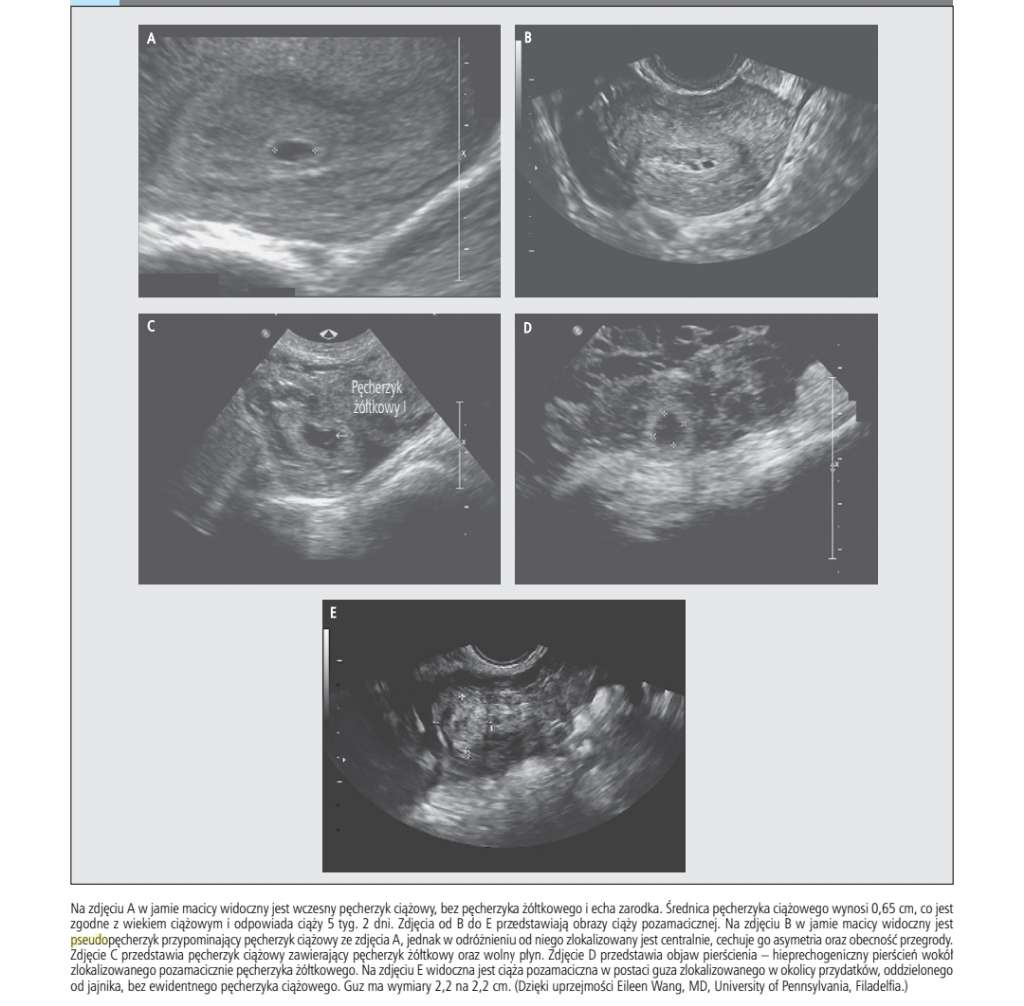

Trochę mi namieszalyscie w głowie z pseudo pęcherzykiem..przy cp

Nie miałam pojęcia o tym ,że może wystąpić przy cp .

Zostawiam tu fragment z medycznego opracowania i nieustannie trzymam kciuki ❤️

Załączniki

• 1ff3ef37-47b7-43bb-ba8f-d1126e68c6ce.jpg

1ff3ef37-47b7-43bb-ba8f-d1126e68c6ce.jpg

No niestety zdarza się to dlatego jestem przewrażliwiona. Jak poczytasz różne źródła to szybkości zobaczysz, że usg jest w stanie wykryć pęcherzyk ciążowy przy becie około 1000 dlatego dziwi mnie tak szybkie wykluczenie cp bo na przykład dla mojej ginekolog pęcherzyk, który pojawiłby się tak szybko byłby powodem do niepokoju